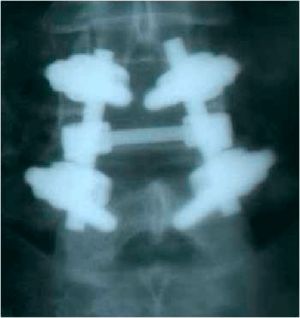

При контрольной рентгенограмме отмечено правильное положение транспедикулярной системы на уровне L4-L5 позвонков. (Рис.9a,b).

Рис. 9 a. Ренгенограмма поясничного отдела позвоночника в боковой (a) и прямой (b) проекции. Транспедикулярная фиксация  L4-L5 позвонков титановой конструкцией, удалена дужка L4 позвонка. Рис. 9 b. Ренгенограмма поясничного отдела позвоночника в боковой (a) и прямой (b) проекции. Транспедикулярная фиксация  L4-L5 позвонков титановой конструкцией, удалена дужка L4 позвонка.

Рис. 9 a,b. Ренгенограмма поясничного отдела позвоночника в боковой (a) и прямой (b) проекции. Транспедикулярная фиксация

L4-L5 позвонков титановой конструкцией, удалена дужка L4 позвонка.